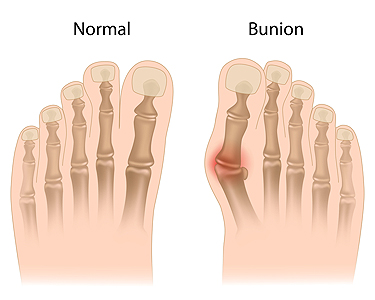

Understanding the Origins and Telltale Signs of a Bunion

Bunions, a prevalent foot condition, can cast a shadow on even the most graceful strides. A bunion, or hallux valgus, emerges when the joint at the base of the big toe shifts out of alignment, causing the toe to lean toward the other toes. The reasons why bunions may develop can vary, often stemming from genetic predisposition. Additionally, wearing ill-fitting footwear that squeezes the toes, or conditions that impact foot mechanics may lead to getting a bunion. The symptoms manifest as a bony bump at the base of the big toe, accompanied by pain, swelling, and redness. As the condition progresses, the affected toe may cross over or under the adjacent toe, causing discomfort and it can be difficult to find comfortable shoes. Recognizing the definition, causes, and symptoms of bunions is crucial in seeking the correct treatment. If you have a bunion, it is suggested that you consult with a podiatrist who can guide you toward the relief and treatment options that are best for you.

If you are suffering from bunions, contact one of our podiatrists of James Kutchback, DPM, CWS-P. Our doctors can provide the care you need to keep you pain-free and on your feet.

What Is a Bunion?

A bunion is formed of swollen tissue or an enlargement of boney growth, usually located at the base joint of the toe that connects to the foot. The swelling occurs due to the bones in the big toe shifting inward, which impacts the other toes of the foot. This causes the area around the base of the big toe to become inflamed and painful.

Why Do Bunions Form?

Genetics – Susceptibility to bunions are often hereditary

Stress on the feet – Poorly fitted and uncomfortable footwear that places stress on feet, such as heels, can worsen existing bunions

How Are Bunions Diagnosed?

Doctors often perform two tests – blood tests and x-rays – when trying to diagnose bunions, especially in the early stages of development. Blood tests help determine if the foot pain is being caused by something else, such as arthritis, while x-rays provide a clear picture of your bone structure to your doctor.

How Are Bunions Treated?

- Refrain from wearing heels or similar shoes that cause discomfort

- Select wider shoes that can provide more comfort and reduce pain

- Anti-inflammatory and pain management drugs

- Orthotics or foot inserts

- Surgery

Bunions

A bunion is a bump that forms at the base of the big toe. Bunions form when the big toe pushes against the next toe, which forces the big toe joint to get bigger and stick out. As a result, the skin over the bunion may start to appear red and it may feel sore.

There are risk factors that can increase your chances of developing bunions. People who wear high heels or ill-fitting shoes are more likely to develop them, in addition to those who have a genetic history of bunions or have rheumatoid arthritis.

The most obvious way to tell if you have a bunion is to look for the big toe pushing up against the toe next to it. Bunions produce a large protrusion at the base of the big toe and may or may not cause pain. Other symptoms are redness, swelling, and restricted movement of the big toe if you have arthritis.

Nonsurgical methods are frequently used to treat bunions that aren’t severe. Some methods of nonsurgical treatment are orthotics, icing and resting the foot, taping the foot, and pain medication. Surgery is usually only required in extreme cases. However, if surgery is needed, some procedures may involve removing the swollen tissue from around the big toe joint, straightening the big toe by removing part of the bone, or joining the bones of your affected joint permanently.

Your podiatrist will diagnose your bunion by doing a thorough examination of your foot. He or she may also conduct an x-ray to determine the cause of the bunion and its severity.